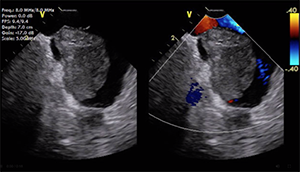

Transthoracic echocardiography (TTE) with bubble echocardiography revealed a large right-to-left shunt at rest, possibly via a patent foramen ovale (PFO). Transesophageal echocardiography (TEE) was deemed risky due to the patient’s borderline respiratory status and large PE. The results of brain CT were negative for stroke. Laboratory workup identified a new diagnosis of factor V Leiden deficiency. The patient’s primary oncologist predicted a high probability of curing her B-cell lymphoma with chemotherapy. The patient was considered very high risk for open embolectomy, right atrial clot removal, and PFO closure by a cardiothoracic surgeon; thus, the structural team was consulted for percutaneous closure of the PFO to prevent further paradoxical embolization.

Drs. Dhamija, Kalra, Kanaa’N: Because the patient is at high risk for intervention, the question is whether the PFO needs urgent or delayed closure. Again, although cardiac MRI can be used to distinguish anatomic differences between a thrombus or a tumor, it can also be used to quantify atrial shunting (however, a flow sequence must be communicated with radiology because the septum is thin and easily missed). Quantifications such as defect size, atrial septal length, and superior and inferior margins are needed to inform the likelihood of successful interventional device closure. However, there is literature describing the use of TTE to guide PFO closure.

If PFO closure is deemed to be urgently necessary, we would pursue ICE. As the moderator noted, the patient is high risk for TEE. ICE would instead require femoral venous access and allow avoidance of the aortoiliac embolus. There is also no need for anesthesia, but costs are higher with single-use catheters for ICE.